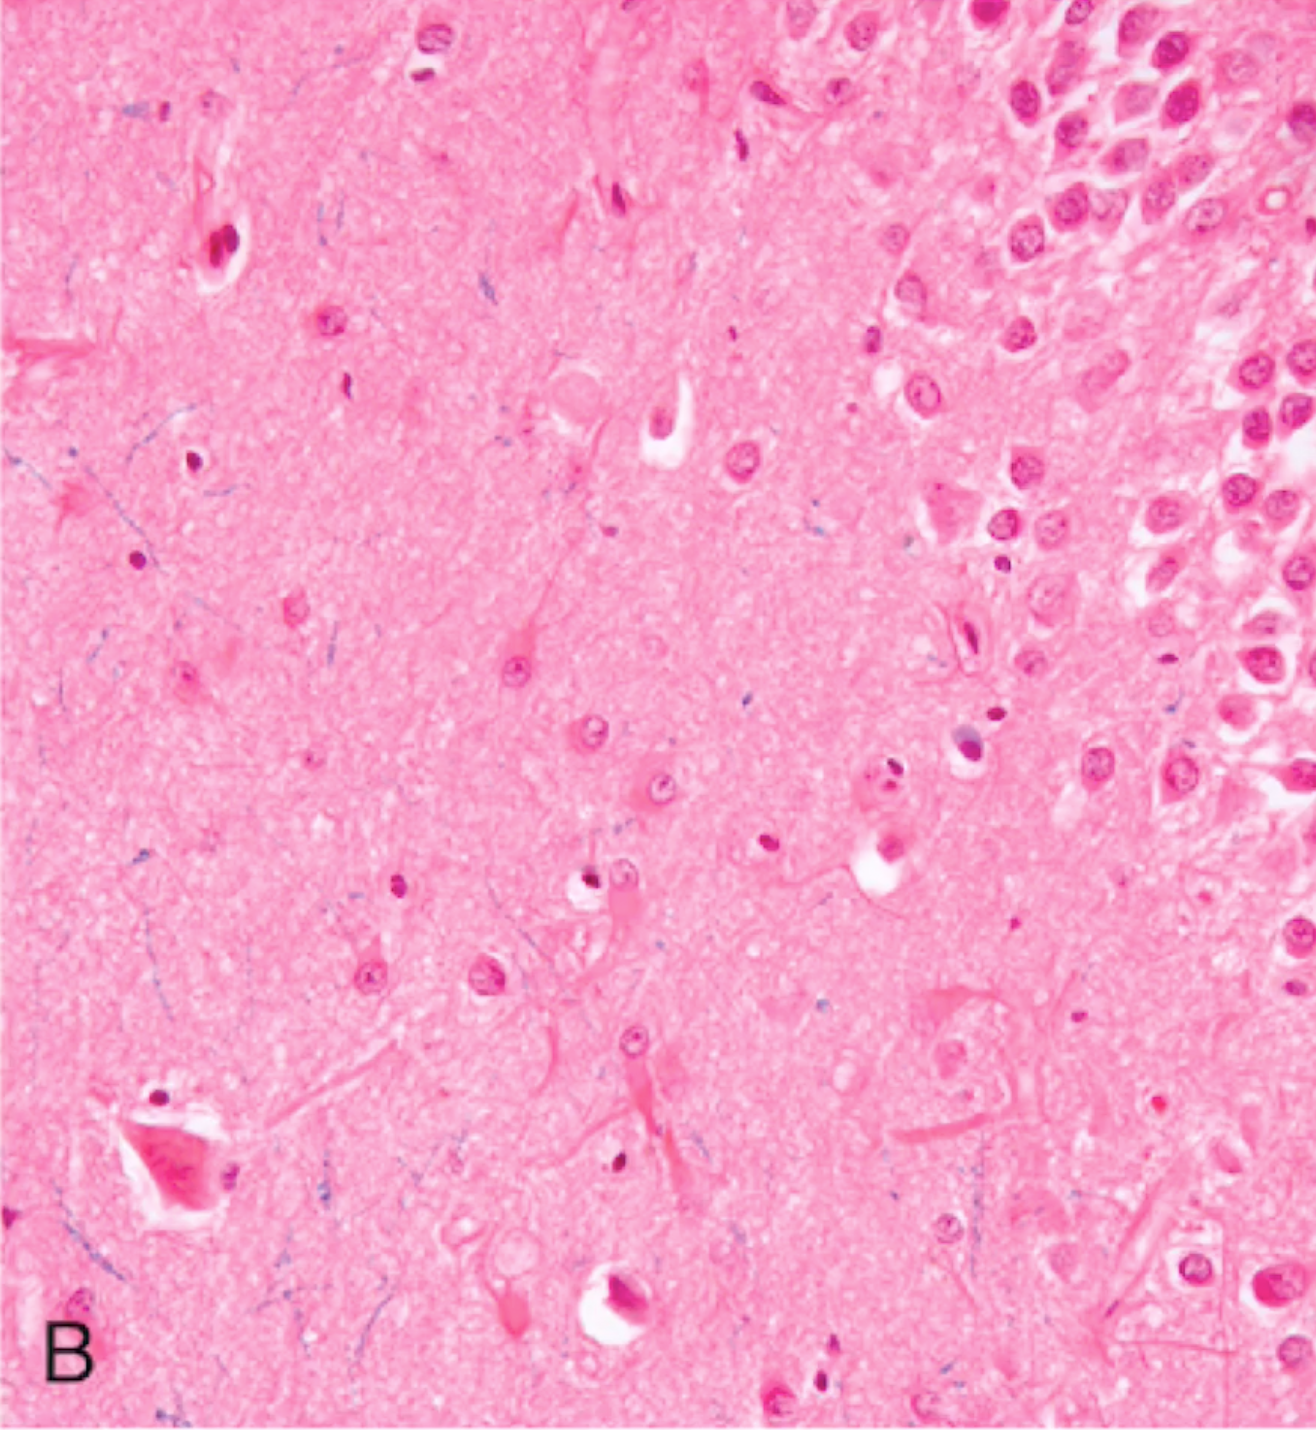

Global Cerebral Ischemia